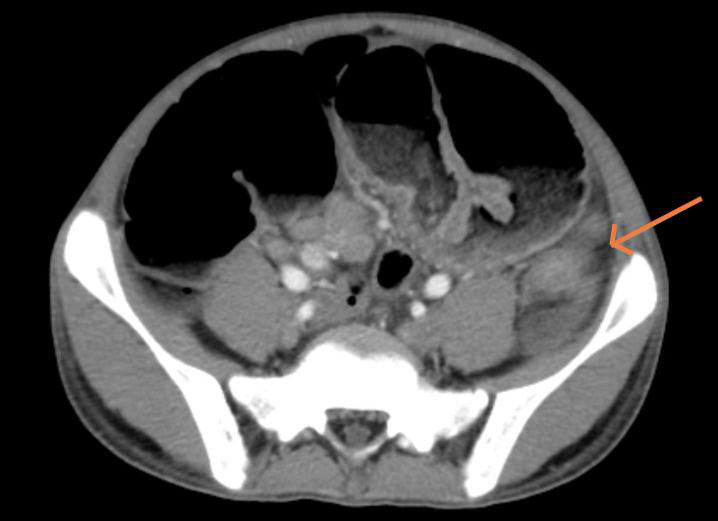

Hình ảnh chụp cắt lớp vi tính ổ bụng cho thấy, các quai ruột non và khung đại tràng của bệnh nhân giãn lớn, đường kính lớn nhất 57mm. Bệnh nhân được chẩn đoán tắc ruột/theo dõi ung thư đại tràng trái và chỉ định mổ cấp cứu làm hậu môn nhân tạo đại tràng trái.